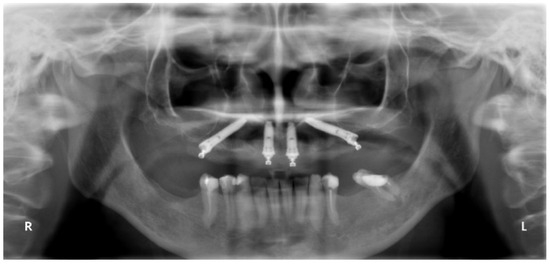

In the present study, short implants measuring 7 mm in length were used. In total, 217 short implants (NobelSpeedy Shorty, Nobel Biocare AB) were placed (21 in the maxilla and 196 in the mandible), out of the total of 157 rehabilitations (20 in the maxilla and 137 in the mandible), with 141 single teeth (16 in the maxilla and 125 in the mandible) and 16 partially fixed prostheses (4 in the maxilla and 12 in the mandible). A case illustration is presented in Figure 3, Figure 4 and Figure 5.

Figure 5. Seven-year follow-up orthopantomograph with the definitive prosthesis connected to a 7 mm implant (4th quadrant).